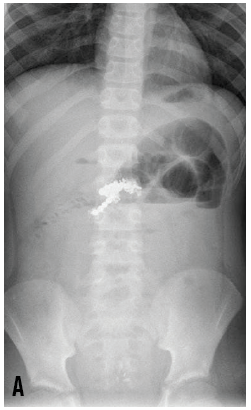

Keren Zhou; Sangeeta Krishna, MD

<p>A 10-year-old boy presented to the emergency department (ED) with a 6-day history of nausea, nonbilious and nonbloody vomiting, and periumbilical pain.</p>